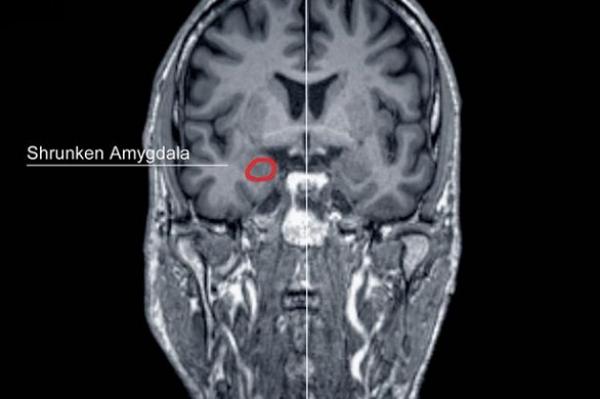

خبراء يجرون اختبارات على دماغ قاتل لمعرفة الأسباب التي تدفع الإنسان لارتكاب الجريمة